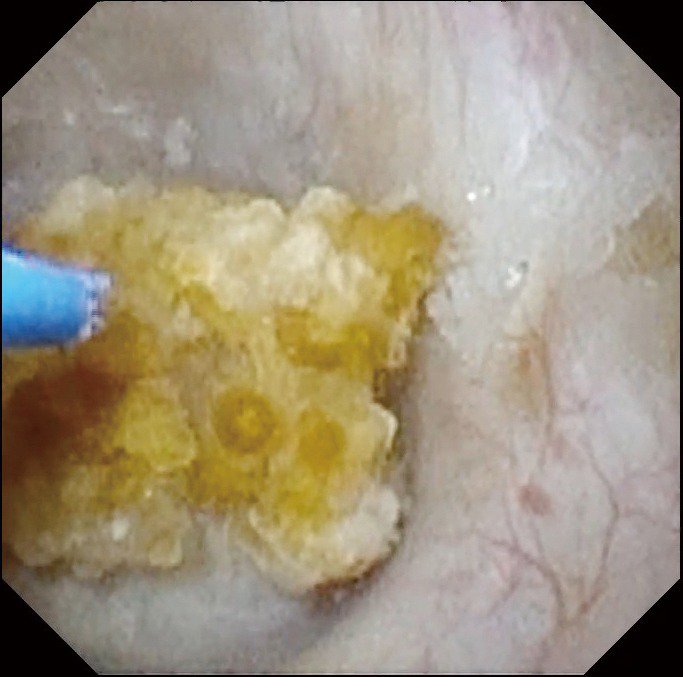

薬で症状の改善が見込めなければ前立腺をとる手術を行うことになり、術式は大きく「内側から少しずつ削る」「レーザーでくりぬく」「尿の通り道を広げる」の3つ。内側から削る方法は出血が多くきれいに取り切れないリスクも高いこと、尿の通り道を広げる方法は再発しやすいことから、当院では「レーザーでくりぬく」方法をお勧めしています。

前立腺はミカンに似た構造で、「皮」と「実」の部分に分かれます。皮と実をレーザーで丁寧にはがし、実の部分だけを膀胱内に落とし込んで、尿道を通れるサイズに刻みつつ摘出していきます。手術時間が長いのが難点でしたが、最新機器を導入したことで、2.5時間から1.5時間まで大幅に短縮されました。